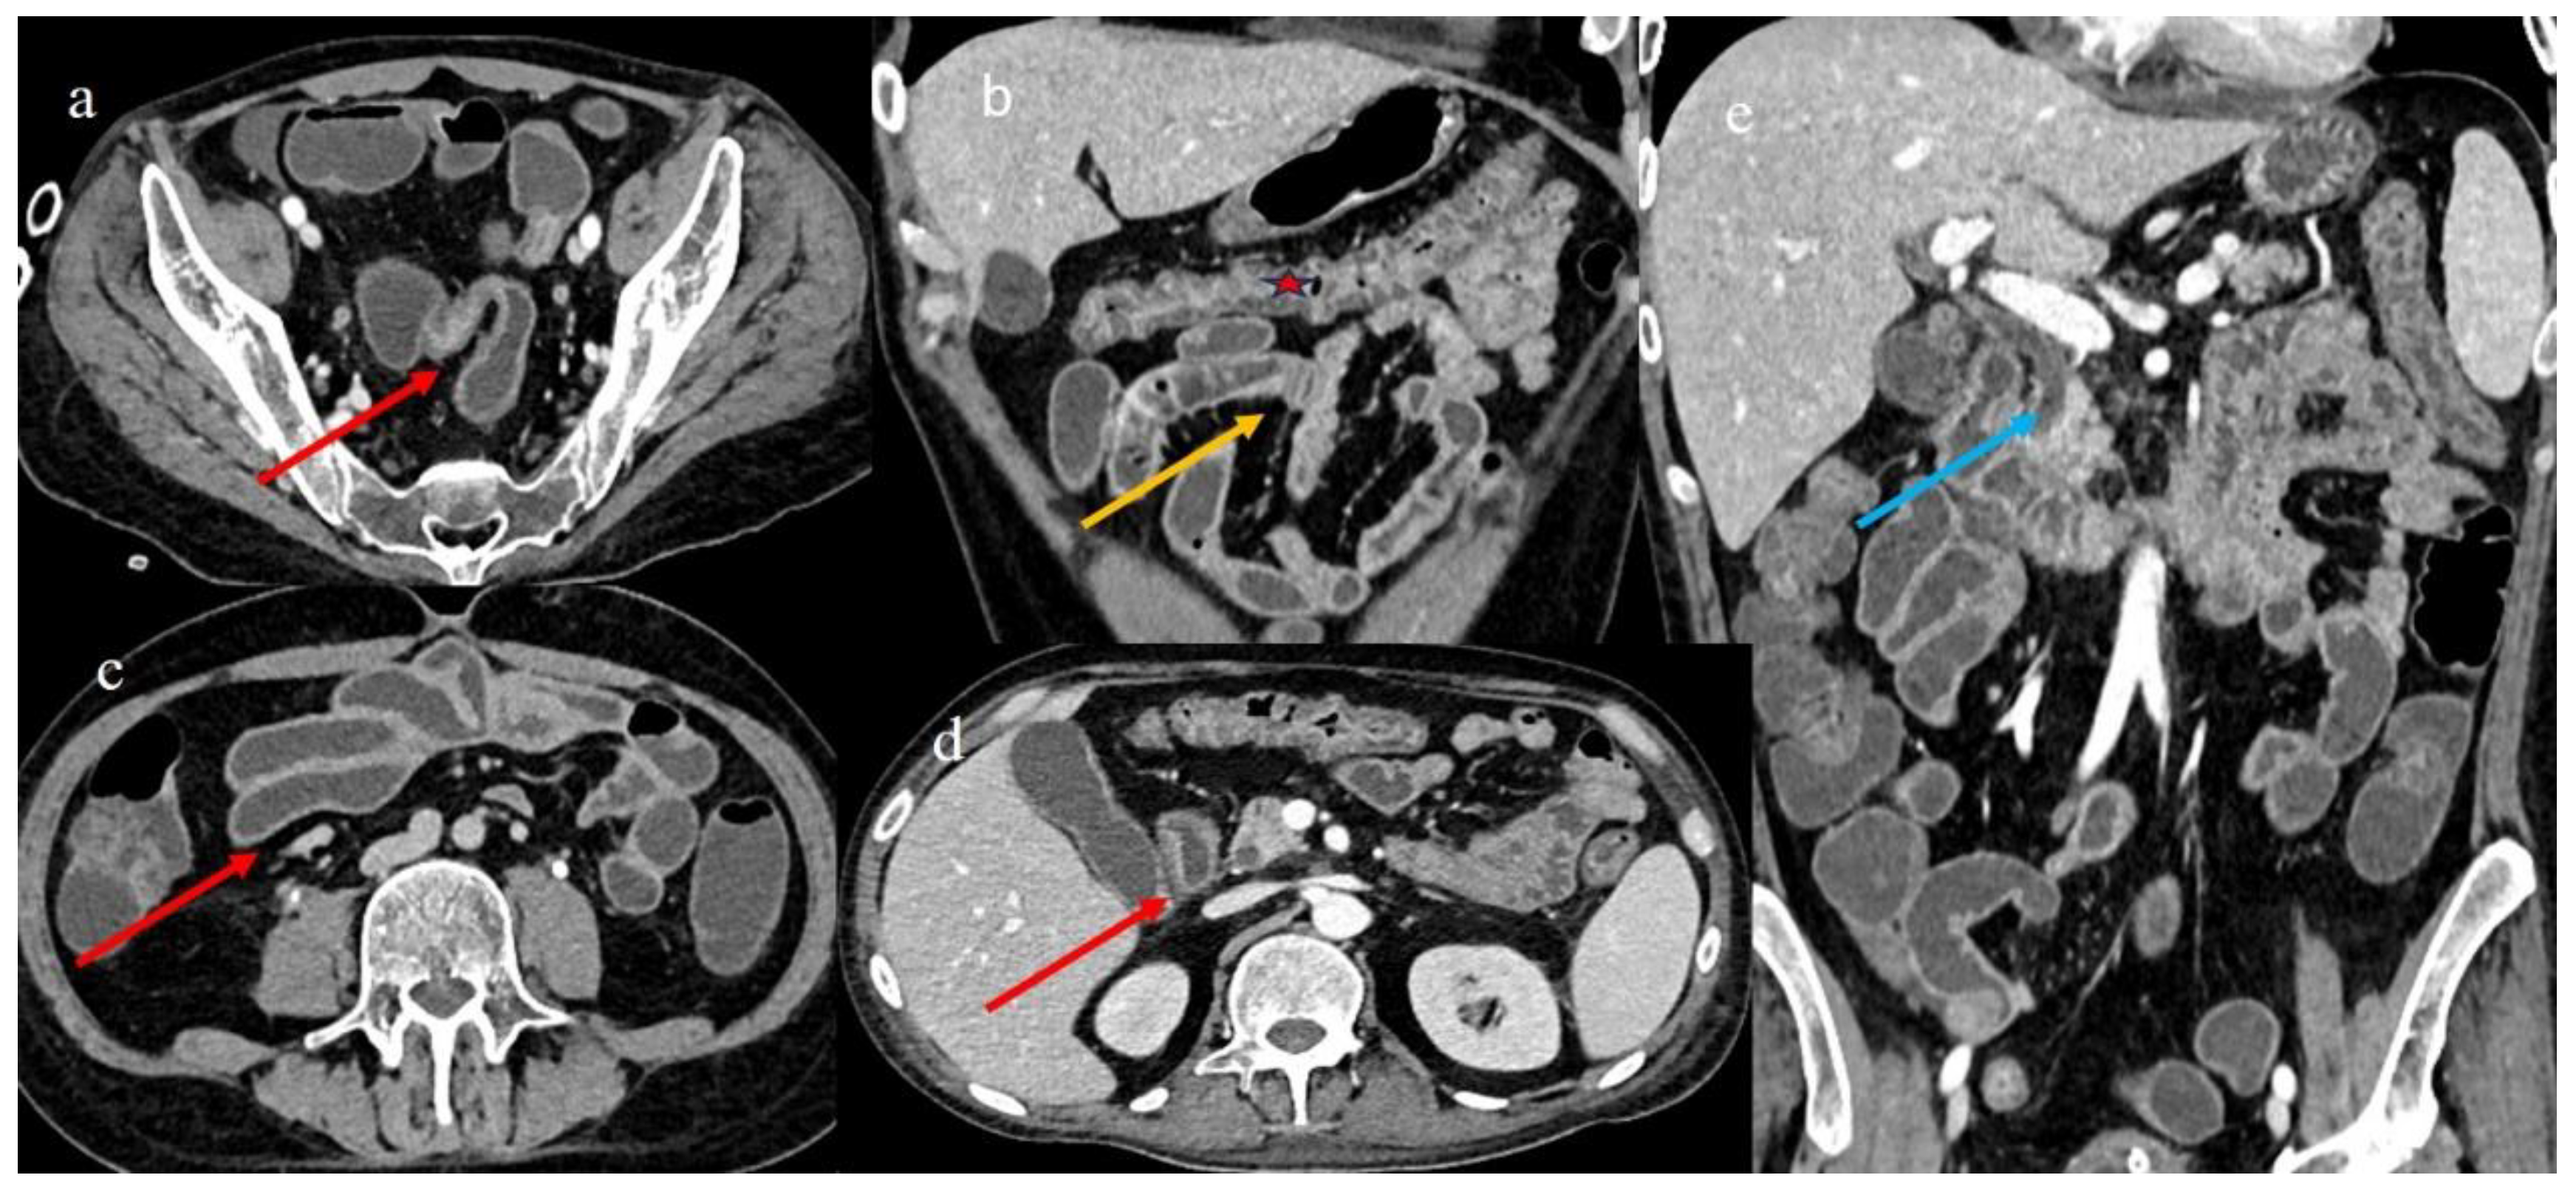

| 1 | P | P | Multisegmental and plurifocal parietal thickness with homogeneous mucosal enhancement on distal ileus | Multisegmental thickness with homogeneous mucosal enhancement | Mild diffuse comb sign and poor reactive mesenteric lymph node | Splenic infarct |

| 2 | P | P | Diffuse parietal thickness with stratified enhancement | Multisegmental thickness with homogeneous mucosal enhancement | Diffuse comb sign and poor reactive mesenteric lymph node | Mild gallbladder thickness and mild biliary tract dilatation |

| 5 | P | P | Multisegmental thickness with stenosis on jejunal loops and SBO and segmental and focal thickness on the terminal ileus and appendix | Diffuse parietal thickness with stratified enhancement | Mild comb sign, poor reactive mesenteric lymph node, small air bubbles in the ascites | Small splenic areas of ischemia |